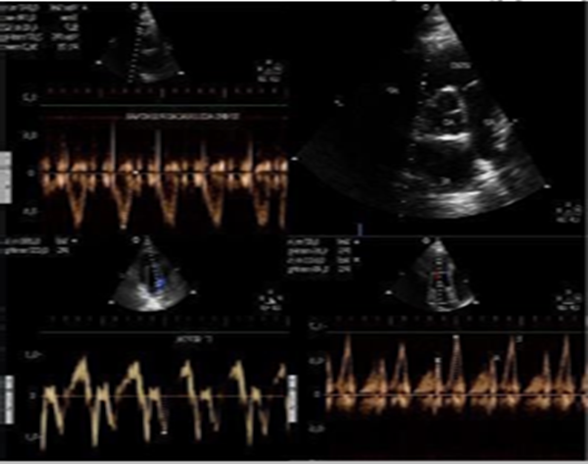

In this study, the main echocardiographic variables assessed were: (a) at the transmitral spectral Doppler, the E wave velocity, A wave velocity, E/A ratio and isovolumetric relaxation time (IVRT); (b) from the mitral annular tissue Doppler imaging, septal e’ wave velocity, lateral e’ wave velocity, mean velocity between septal e’ and lateral e’; (c) E/e’ ratio (E wave velocity/mean velocity between septal e’ and lateral e’); (d) acceleration time at the right ventricle outflow tract (AcT), measured on the short axis view toward the heart base vessels, at the tip of the pulmonary valve leaflet, from the start to the peak of the systolic flow; (e) left atrial volume (LAV) and (f) pulmonary artery systolic pressure (PASP), measured by the tricuspid regurgitation peak velocity, when present (Figures 1 and 2)